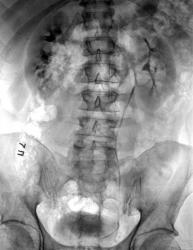

Экскреторная урография

Пациент обратился в приемное отделение, с клиникой почечной колики, в экстренном порядке был госпитализирован. Было сразу сделано УЗИ абдоминальное+почки, где выявлено каликопиелоэктазия справа. Мы же сразу сделали экскреторную урографию, в данном случае получилась экстравазация рентген-контрастного вещества. Обзорную урограмму я ни стал скидывать поскольку там не визуализируются рентген контрастные тени на фоне кишечного содержимого. Урологи сразу взяли его в операционную где был установлен стент в мочеточнике.

Интересное наблюдение! Мне видится гидронефротическая трансформация правой почки. Затекание контраста за пределы правого мочеточника ("мочевой затек") в верхней трети. Повреждение мочеточника камнем (ни разу не встречал)? А травмы случайно не было? Не все благополучно и вокруг правой лоханки. Те же тени контраста за пределами мочевыделительной системы. Не дифференцируется правая поясничная мышца. Все таки склоняюсь к мысли о травме правой лоханки и правого мочеточника. Если бы данная картина была при МКБ, то почка бы молчала (блок почки). Здесь же функция почки полность сохранена. Да- это травма!

В заключении я не исключил наличие не рентген-контрастного камня в правом мочеточнике, хотя при уретероскопии урологи прошли всего 4-5см, от устья, в дальнейшем они подконтролем рентгена установили стент.

Уважаемый Андрей Юрьевич по поводу экстравазации(до словно ( это вытекание какой-либо жидкости из сосудов в окружающие ткани в результате травмы, ожога, воспаления или аллергии), в данном случае мы предположили как результат воздействие камня на стенку мочеточника.

Какие либо травмы данный пациент отрицает.

Заключительный диагноз выставленный урологами звучит так: Уролитиаз. камень н/3 правого мочеточника. Рицидивирующая почечная колика справа.

Я ещё раз повторяю травм ни каких не было у данного пациента. Стент ему будут убирать в концу данного месяца.

Сегодна проконсультировался со своими урологами. Случаи повреждения стенки мочеточника камнем имеют место в медицинской практике, но крайне и крайне редко. В представленном случае урологи прошли катетером 4-5 см от устья мочеточника и поставили стент(как сообщил коллега). Т.е. камень должен быть в нижней трети мочеточника. При этом мочевой затек имеется в верхней трети и в лоханке! Травма это. Какая, не знаю. Я не прокурор, чтобы разбираться. И еще, сегодня смотрел пациента с камнем в юкставезивальном отделе левого мочеточника. 10 мм камень лежит в течении 1,5 лет. Почка блокирована. Но повреждения стенки камнем отсутствует (пролежень).

При острой обструкции мочевых путей возникает резкое повышение давления в чашечно-лоханочной системе почек. которая может самостоятельно понизиться в результате пиелосинусной экстравазации мочи при разрыве форниксов.

На третьей рентгенограмме видим: Больной встал на ноги и контраст потёк вниз до самого моч. пузыря. Мочеточник нигде не расширен, что указывало бы на наличие препятствия. Параллельно вниз по клетчатке двинулся экстравазированный контраст.

Нельзя не отметить паранефрит – вероятно вследствие экстравазации мочи (сколько она уже продолжается?) и однажды упомянутый тубулярный рефлюкс, который может быть следствием повышения давления в полостной системе справа, но и признаком патологии сосочков почки тоже может быть (папиллита например).

Мне лично более всего не нравится нижний полюс правой почки. Какая-то мазня там уже с 7'. Ах как не хватает обзорной урограммы! Возможно, здесь и происходит эта самая экстравазация. А в целом картина напоминает феномен Olsson характерный для туберкулезного поражения почки. Что нам остаётся: поискать каверну (возможно, она наслаивается на среднюю группу чашек), свищ. Без томографии (с новым контрастированием) и обзорной урограммы достоверно не определить. И про посев мочи можно напомнить урологам, а можно тому сотруднику – хозяину почки.